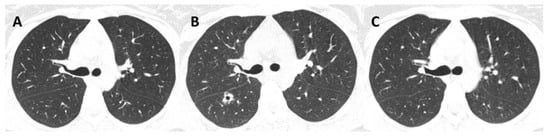

3.3. Radiological Patterns

| 14 (2018) | Female | 20 | Contact with diseased cats | Disseminated | Skin, lungs, bones, upper airways | HIV (CD4 = 56 cells/mm3) Alcoholism | Pneumocystis pneumonia | Cavitation; reticulonodular infiltrate; consolidation | Sputum | ITZ; AmB; PSZ | Cure |